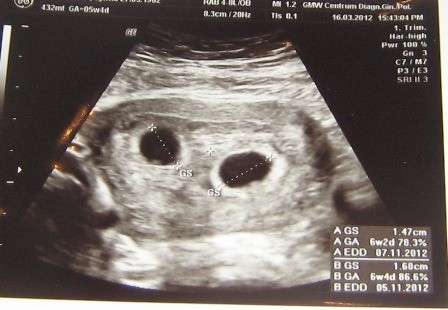

Zobacz załącznik 447736 To moje dwa maleństwa, proszę zostańcie u mamusi w brzuszku do listopada!!!!

Ehtele- u mnie właśnie to samo są 2 pęcherzyki wielkości już na 6 tydzień-co jest niemożliwe, ale w środku gin ledwo, ledwo coś tam dostrzegł, ale powiedział, że nie mam się tym martwić!!!!za 10 dni mam wizytę i mam nadzieję, że usłyszę serduszka i wtedy odetchnę.....